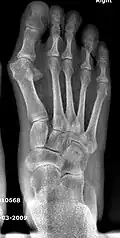

Fig. 5 Stress fracture of the second metatarsal bone

5. Second metatarsal stress fracture (Fig. 5)